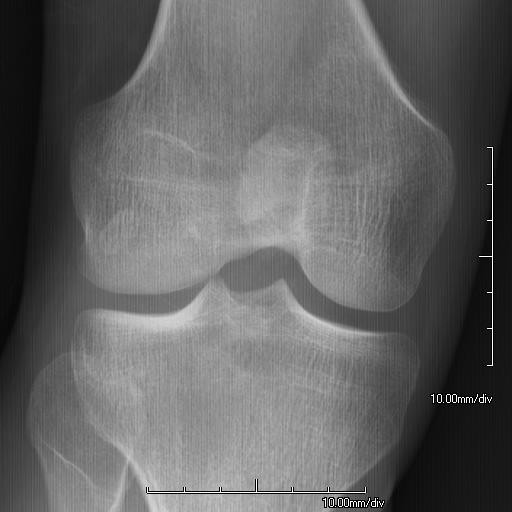

hypoplastische

patella |

BotafwijkingenDe knieschijf (patella) kan misvormd zijn,

onderontwikkeld (hypoplasie) of geheel ontbreken (aplasie). Dislocatie van de

patella komt vaak voor. De ellebooggewrichten zijn abnormaal (arthrodysplasia)

en staan soms in gebogen stand gefixeerd. Op de heupbeenderen kunnen hoornvormige

botuitsteeksels zitten (iliac horns, bij 70%). Rugpijn door afwijkingen aan

de wervelkolom (spondylolisthesis) komt regelmatig voor.